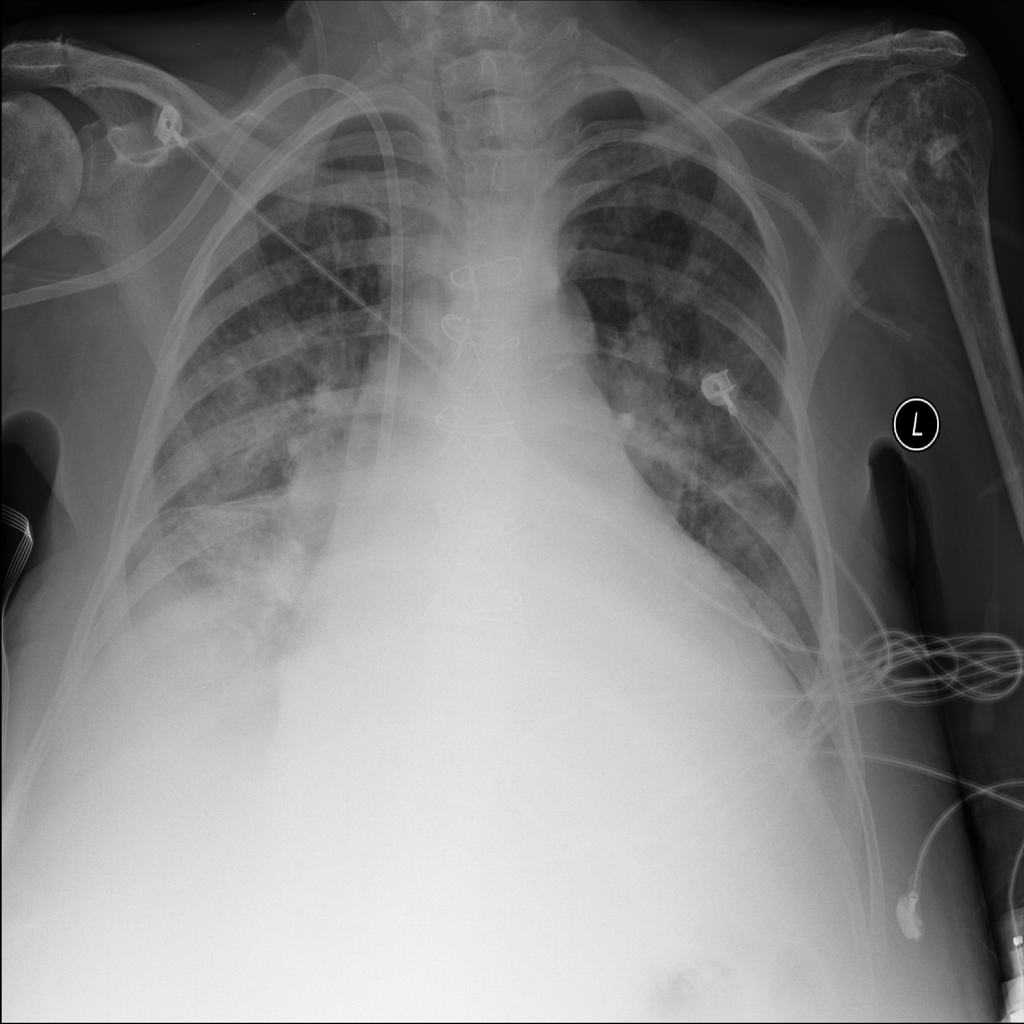

PAT-531A · IMG-006Consolidation

PAT-531A · IMG-006

PA